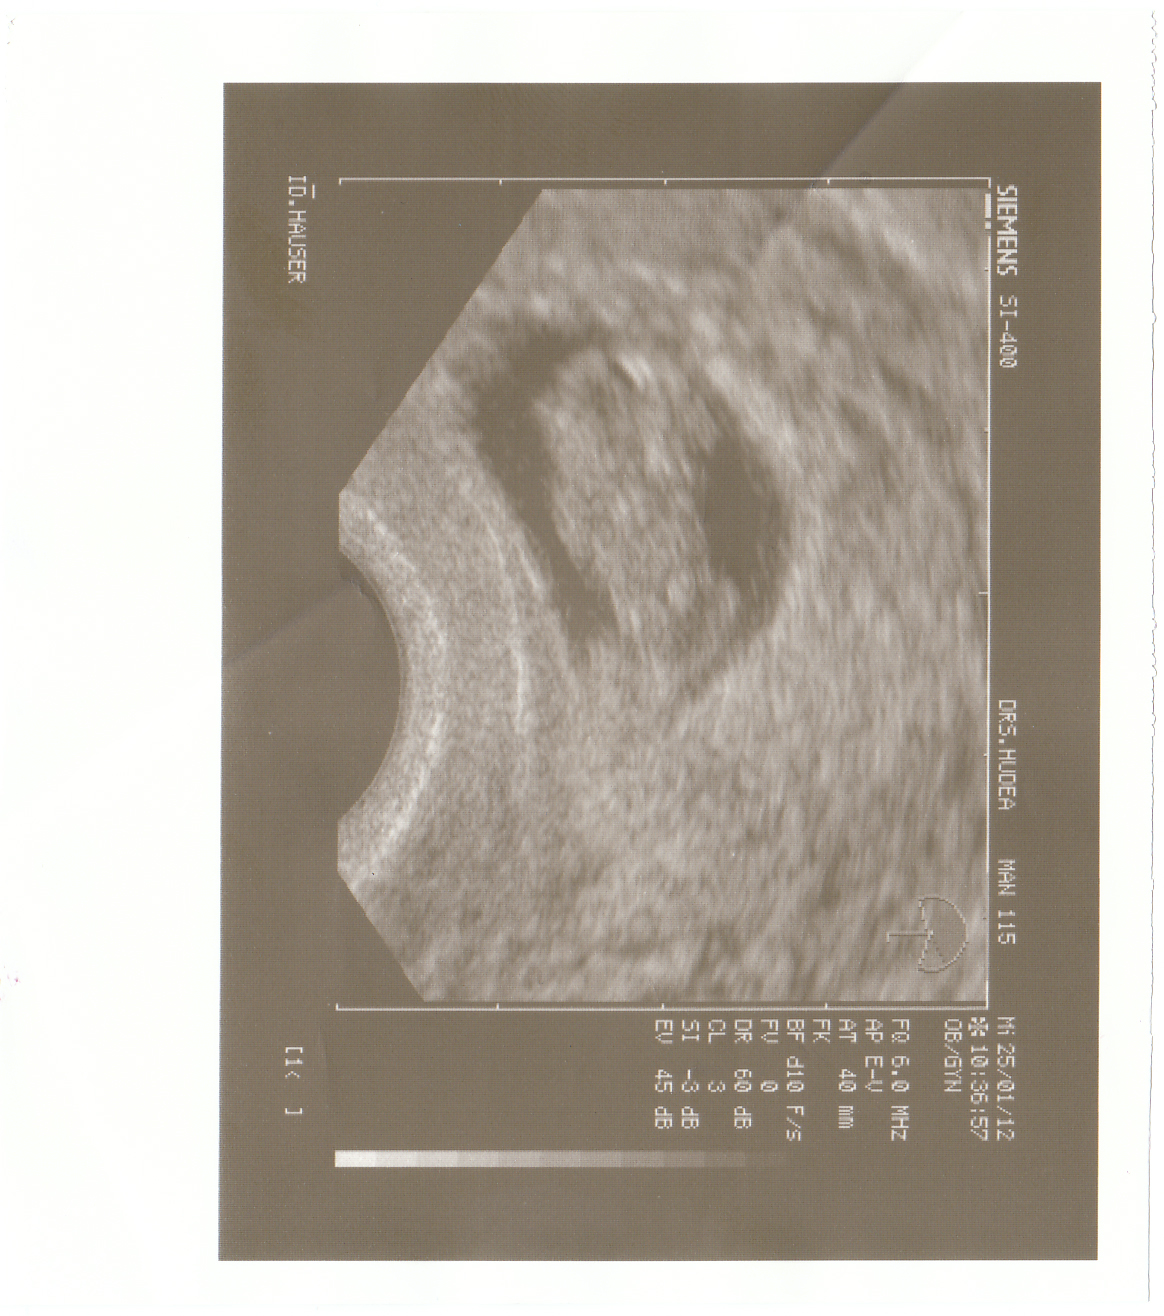

25.01.2012 – Das erste Foto von dir..